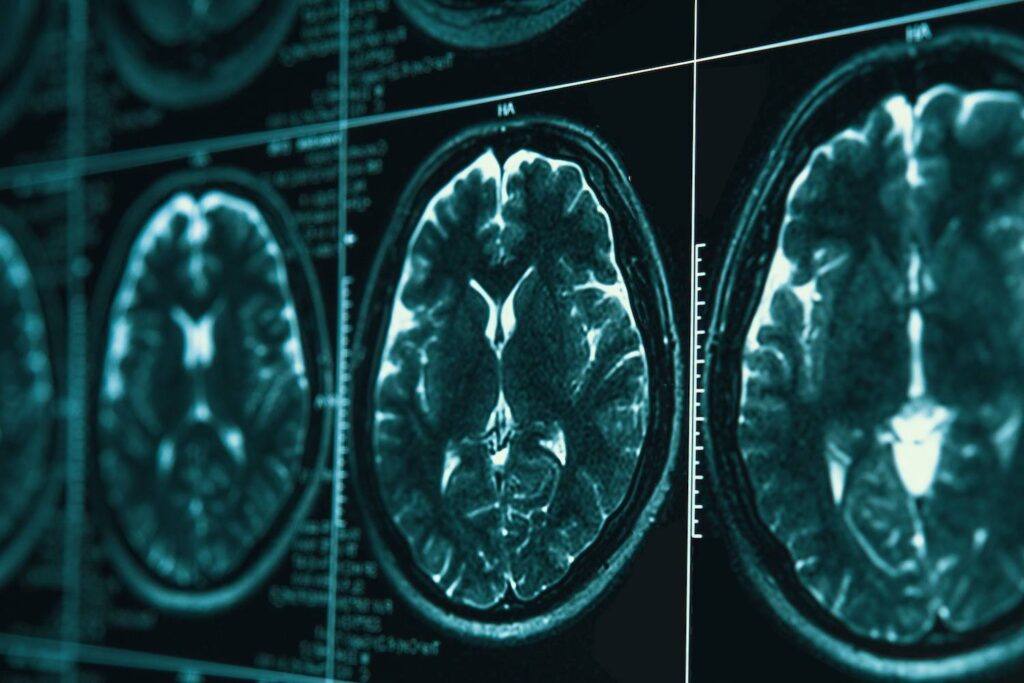

Wenn die Symptome von Alzheimer frühzeitig erkannt werden, haben die Patienten bessere Chancen auf eine wirksame Behandlung. Die Behandlung von Alzheimer und anderen Demenzerkrankungen ist in der Regel in den frühen Stadien der Krankheit am wirksamsten. Eine MRT- Untersuchung kann eine frühzeitige Diagnose ermöglichen.

Für eine Früherkennung von Alzheimer kann eine MRT-Untersuchung des Kopfs behilflich sein.

Außerdem können Ärzte Hirnuntersuchungen durchführen, z. B. Computertomographie, Resonanztomographie oder Positronenemissionstomographie. Das Ziel dieser Untersuchungen ist es, andere mögliche Ursachen für die Symptome auszuschließen.

Die MRT kann auch helfen, indem sie zeigt, wie sich das Gehirn einer Person im Laufe der Zeit verändert, wenn die Untersuchung regelmäßig wiederholt wird. Obwohl die Anzeichen für eine Schrumpfung nicht auf eine spezifische Diagnose hindeuten, können sie die Diagnose von Alzheimer oder anderen ähnlichen Erkrankungen unterstützen. (7)